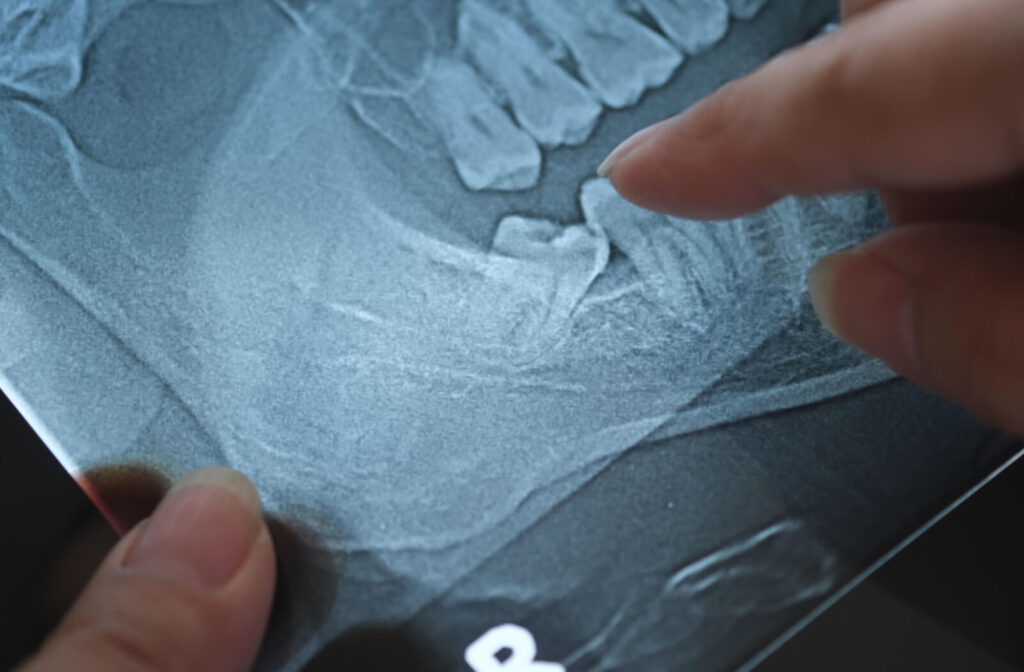

A good indicator of their growth is regular dental X-rays during adolescence, which can reveal a lot about whether these molars are developing properly. These X-rays can show your dentist the position, angle, and potential pathway of your wisdom teeth long before they break through the gum line.

X-rays are helpful for monitoring the growth of wisdom teeth. They provide a clear image of your jaw and indicate the position of your wisdom teeth. Panoramic X-rays are beneficial because they show the entire mouth in one image, allowing your dentist to see:

- The position and angle of developing wisdom teeth

- Available space in your jaw

- Proximity to nerves and adjacent teeth

- Signs of potential impaction